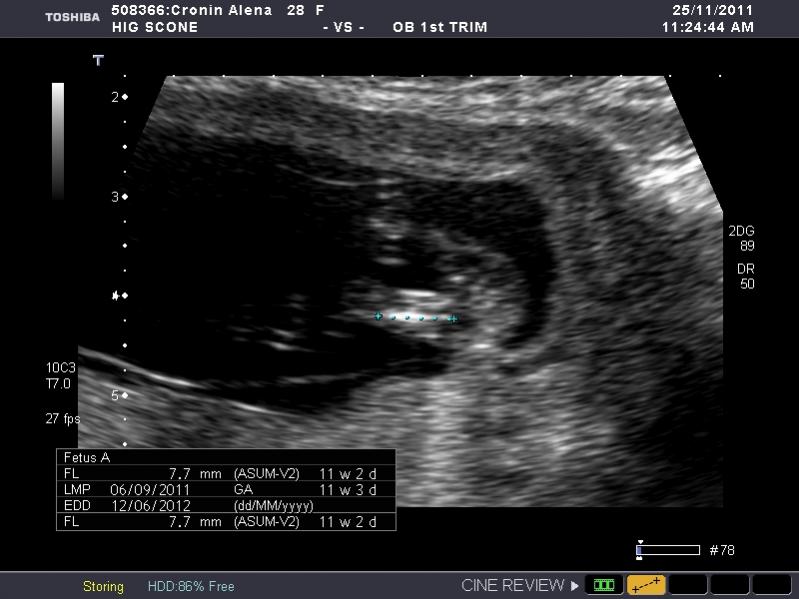

I have heaps of photos and I don't know what I am looking at so if the photo I post isn't showing anything let me know and I will try another. I am nervous as anything because I so so want a girl, but of course would still be happy with a boy. The ultrasound tech wouldn't guess.

So what is your guess.